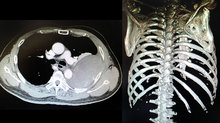

湯姓男子被轉院後,重新接受了相關檢驗,並進一步使用顯影劑做電腦斷層掃描,檢查發現他的血小板只剩7萬,一般成人的血小板正常值應該要有15至40萬,且影像上看到多根肋骨節狀骨折的連枷胸,併發非常罕見的巨大肋膜下血腫,檢查當下還在急性出血中,因此徵求病人及家屬同意後,立即進行了緊急手術治療血胸,並以肋骨固定手術降低骨折疼痛、肺臟合併症,縮短住院時間,並挽救了湯姓男子一命,術後照護一切順利,也未發生感染問題。